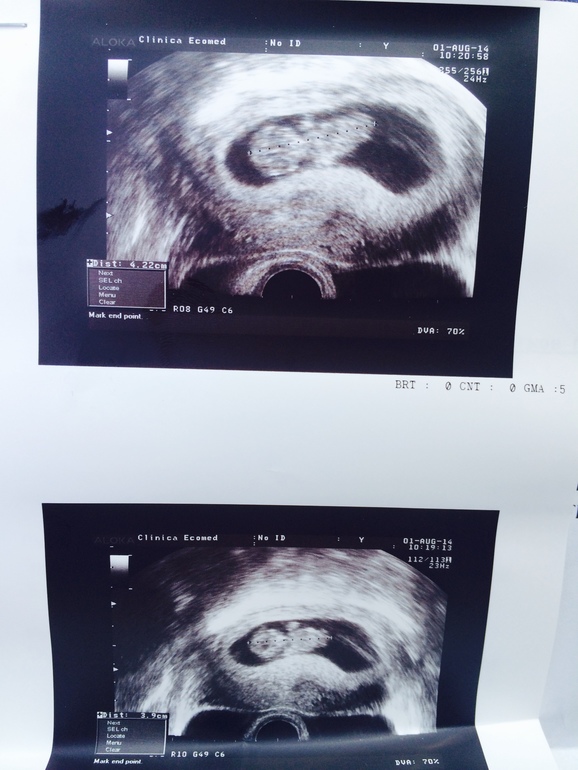

УЗИ показало, что срок 4 недели, но есть угроза и теперь я должна три дня минимум провести в постели с кучей лекарств. Конечно, я не выдержала и 2-х дней и снова пустилась в работу. А после работы мне вздумалось еще и круги по парку нарезать, гуляя пешком. И снова кровь и этот страх! И опять прием у гинеколога и УЗИ. Не повторяйте моих ошибок!!!

Сегодня настал день нашего третьего УЗИ, гинеколог назначила. Идет 9 эмбриональная и 11 акушерская недели. Конечно, у всех к этому времени только первое УЗИ случается, но у меня угроза и поэтому такой мониторинг. На УЗИ мы пошли вместе с будущим папой. Нам дали послушать биение сердца нашего малышика. Мы смогли хорошо его разглядеть. Он так смешно дергал ручками и ножками, танцевал джигу-дрыгу в моем животике))) Мужа это очень впечатлило, он еще пару раз за день потом это вспоминал и даже показывал, как он двигался! Не зря я его взяла с собой. Хотелось, чтобы наш ребенок перестал быть для него чем-то эфемерным, а перешел в разряд реального.

Итак, нам сказали, что ребенок растет и развивается очень хорошо и даже с опережением, у него длинные ноги и руки, будет высокий малыш, в папу. Угроза пока сохраняется, и я должна быть очень осторожна. Теперь меня отправили на постановку на учет, выбираю себе врача. И недели через 2 идем на 1 скрининг.

Ух, самое страшное позади, и я теперь так счастлива. Смотрю на снимок УЗИ, где уже очень хорошо все видно и понятно, и сердце заходится радостью! Я переполнена впечатлениями.